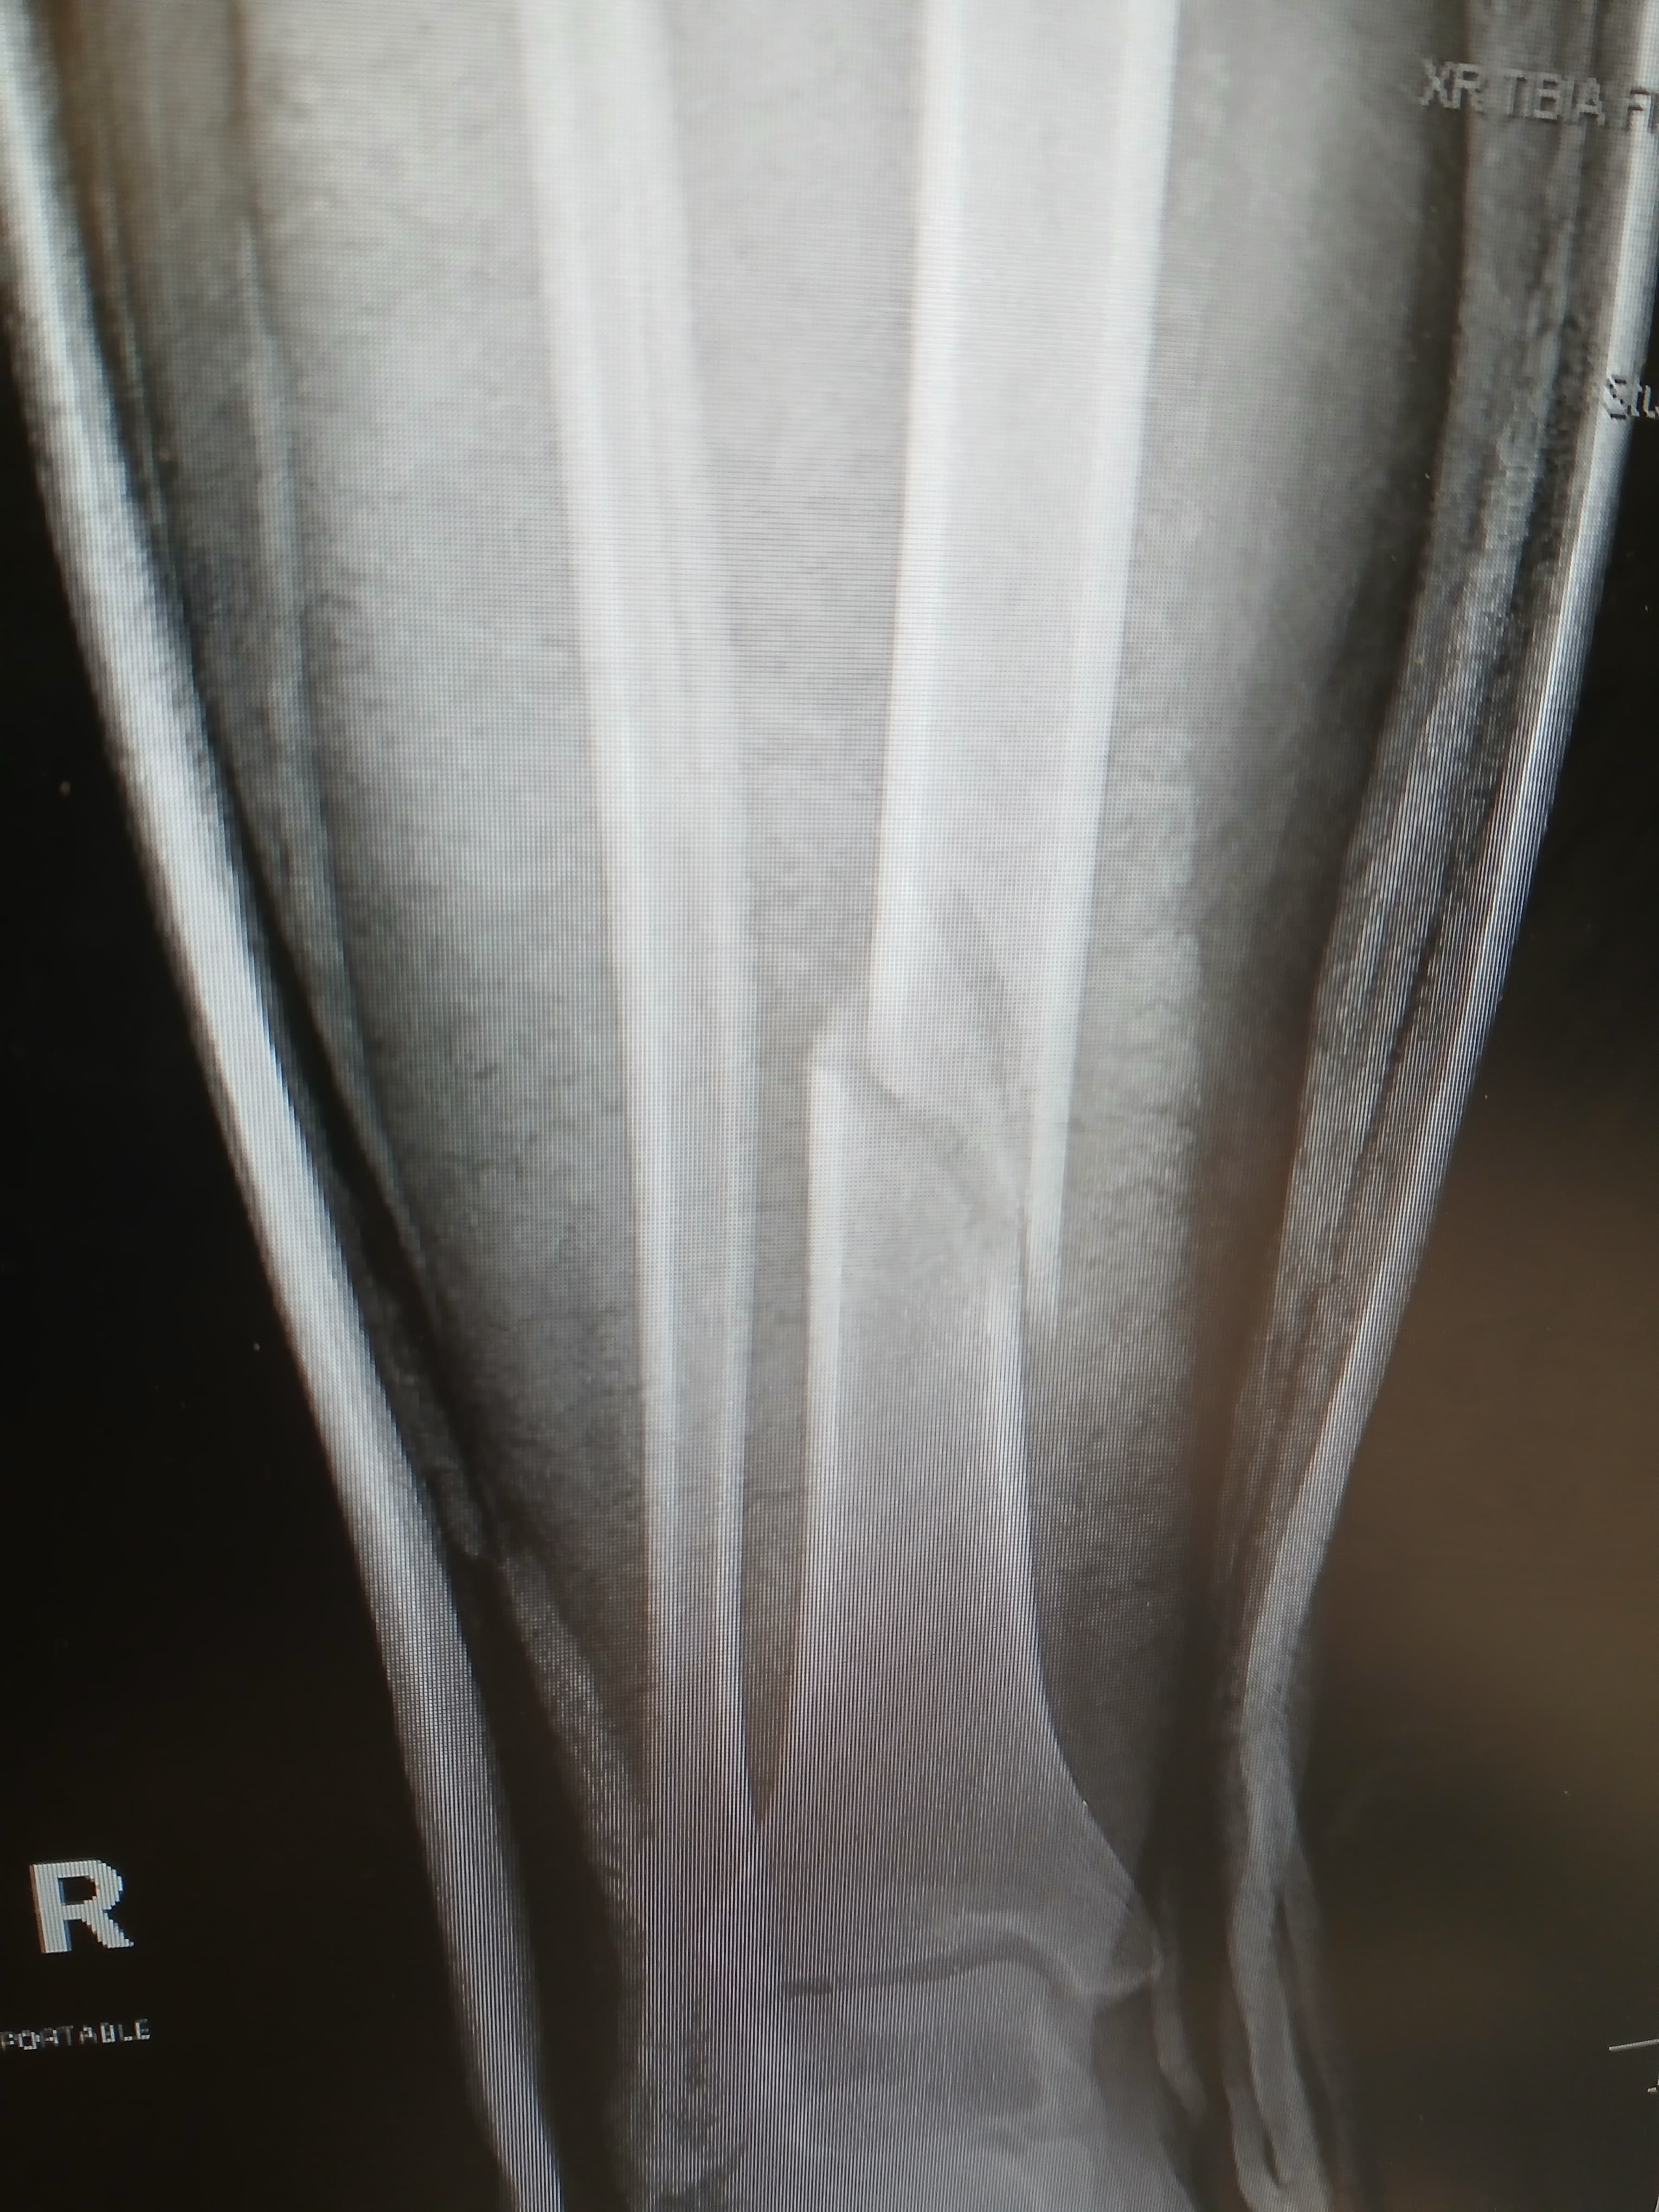

My name is Cristal, and I recently slipped on ice during a bad storm, breaking my leg in two places. The accident happened so quickly, and it has completely changed my daily life. I am now facing a long recovery, unable to work, and struggling to manage even simple tasks on my own. The pain and stress have been overwhelming, and I am worried about how I will keep up with my 2 children, medical bills and rent while I heal.